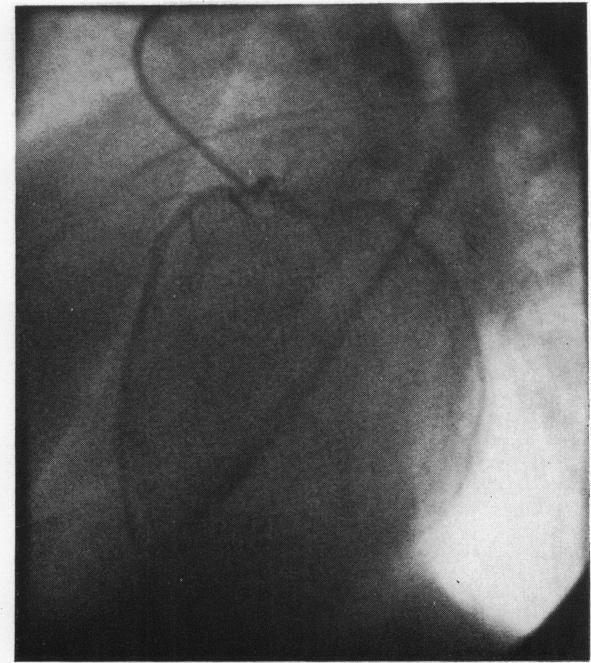

Selective coronary angiography in primary myocardial disease.

Br Heart J. 1973 Feb;35(2):165-73. doi: 10.1136/hrt.35.2.165.